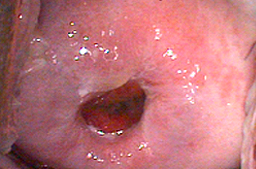

Tratamiento mediante fotovaporización con láser CO2.

• Fotovaporización con láser CO2

• Cicatriazación al mes del tratamiento